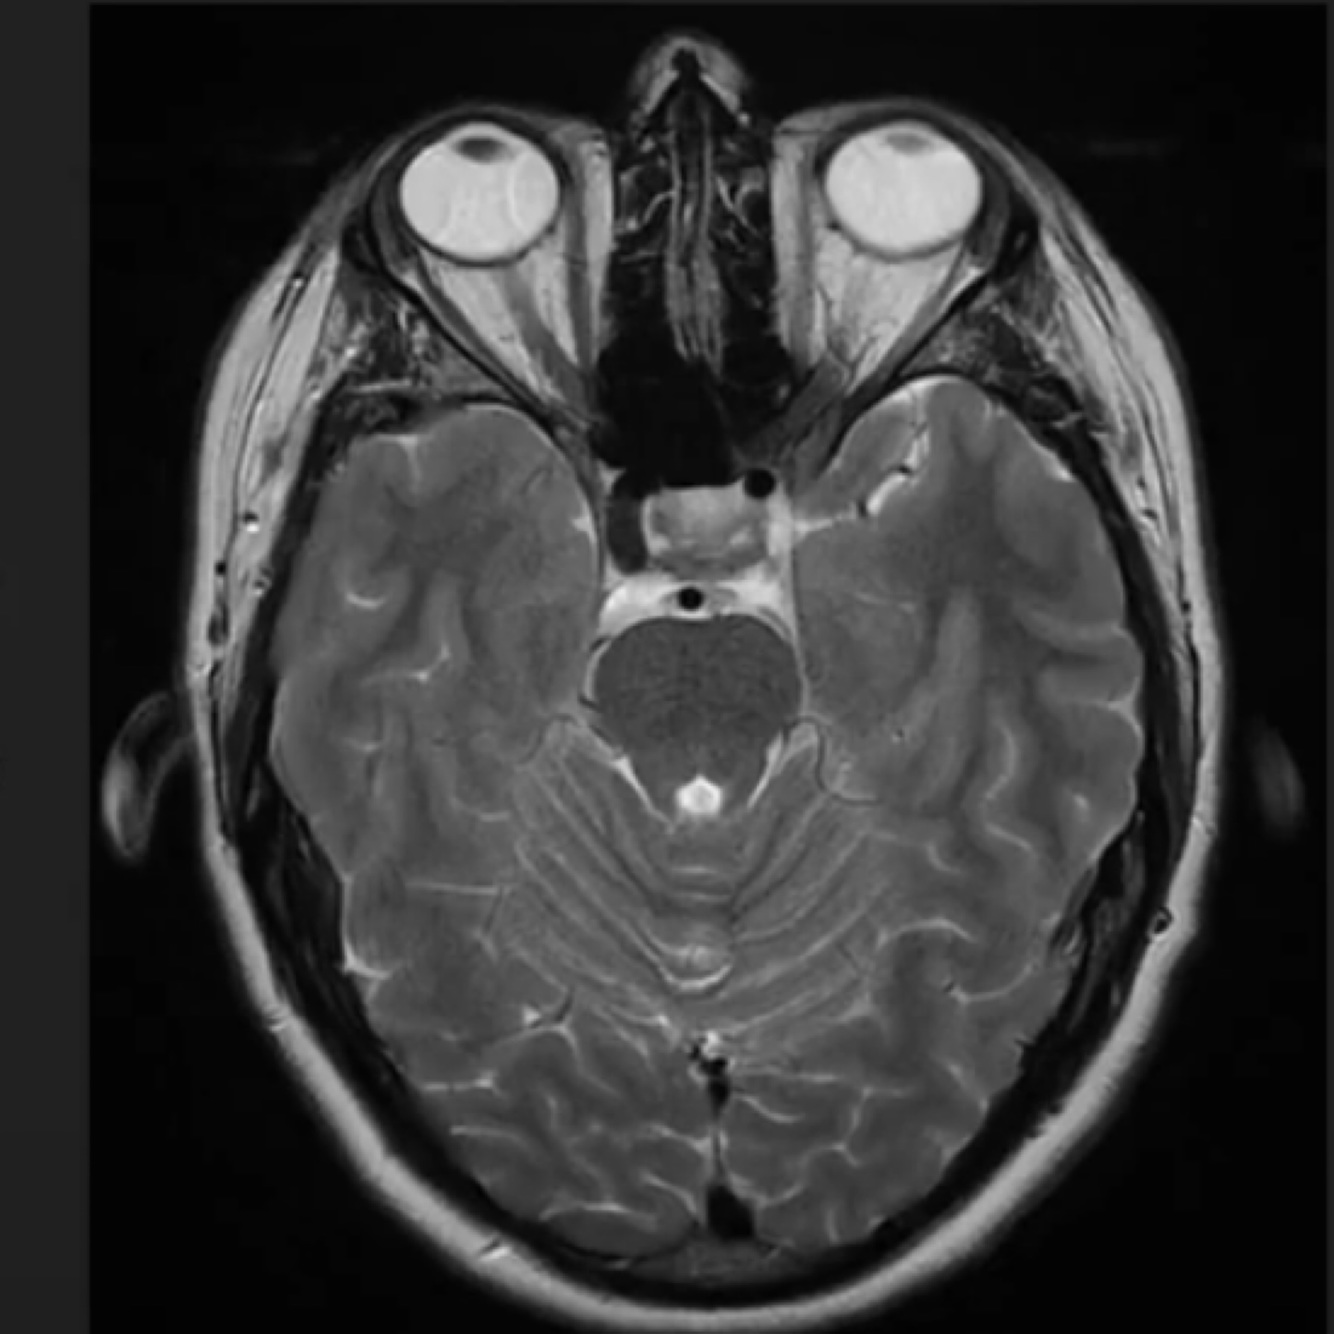

Which structure is filled with CSF and surrounds the brainstem and what is it called, and which structure is the fourth ventricle?

) basal cistern